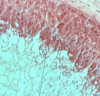

Toxoplasma cyst in brain

Toxoplasma cyst

Cross section, Vessels are seen below!

Toxoplasma cyst

Brain cells around

Toxoplasma cyst

Hematoxilin Eosin staining

- Brain cell of mouse because it is cross section of it

- Vessel

- Toxoplasma cyst

Brain cell

Toxoplasma - Bradyzoites